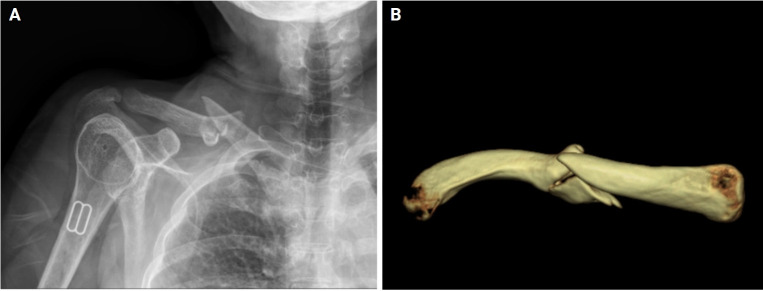

Brachial plexus paralysis is a rare but serious complication following clavicle fractures that is often linked to neurovascular compression, with an incidence of 0.5% to 9.0%. This report presents a case of brachial plexus paralysis in a 61-year-old woman after surgical fixation of a deformed mid-clavicle fracture with a metal plate. Revision surgery was performed to address the paralysis, involving removal of the metal plate, arcuate osteoplasty to create a smooth arch beneath the clavicle, and re-fixation of the plate with adjusted superior angularity. We used this approach to relieve neurovascular compression and restore thoracic outlet space. Over a period of 1 year, significant recovery and successful fracture union were achieved. This case demonstrates that managing brachial plexus paralysis with revision surgery and osteoplasty can effectively restore both neurological function and bone healing.